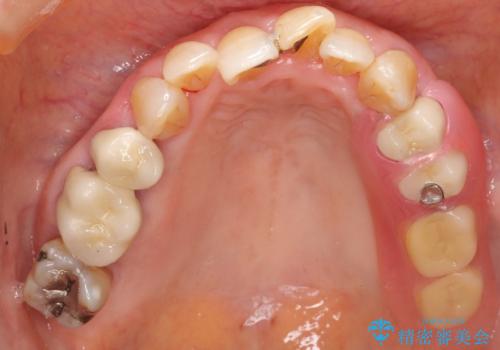

歯ぐきから血が出る、歯ぐきが腫れている 80代女性

- 歯ぐきからの出血と腫れを主訴に来院された患者様です。

プラークコントロールが非常に悪く、全顎的な歯周病に罹患していました。

「抜歯したくない、インプラントは嫌」という患者様のご希望とご年齢を考慮し、可及的な骨外科処置や根分割術によりできるだけ今ある歯を残す治療方針をたてました。

保存不可能な左上の奥歯2本(左上67)は抜去し、ノンクラスプデンチャーをいれることにしました。